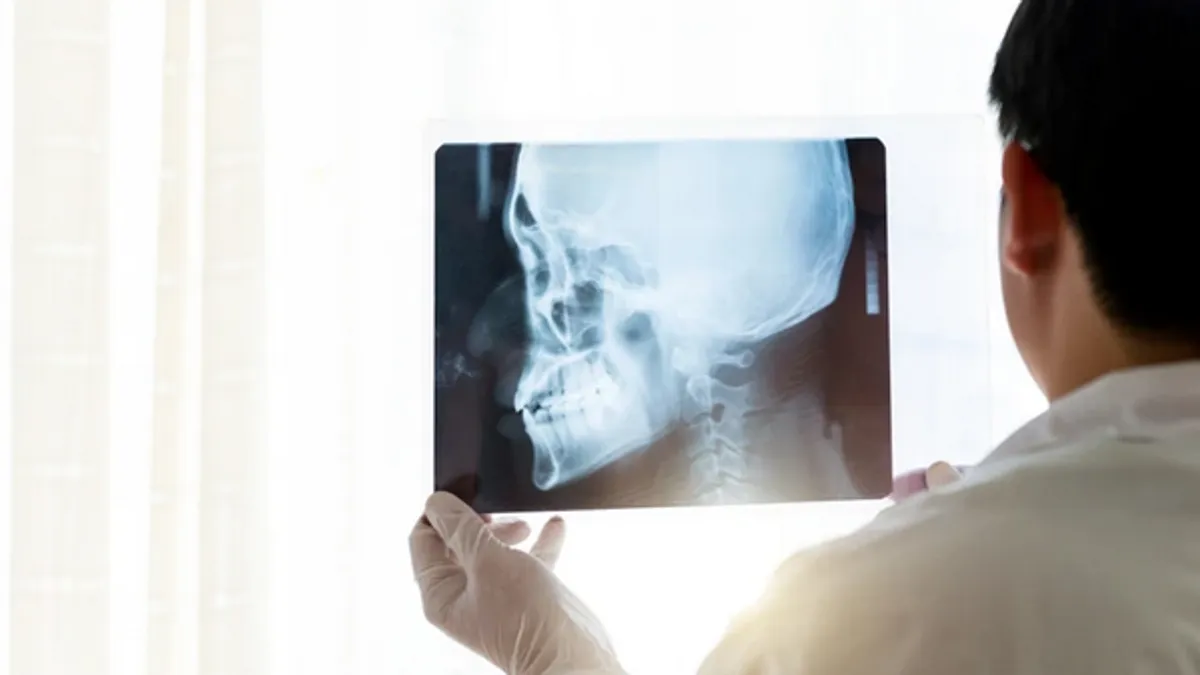

CT snimak otkrio je ozbiljnu deformaciju pršljenova C3, C4 i C5, dok su svi ostali testovi – uključujući mišićnu snagu i funkciju kranijalnih nerava – bili uredni. Zbog ozbiljnosti stanja, ljekarski tim odlučio se za trofaznu hiruršku intervenciju tokom koje je odstranjen deformisani dio kosti, pa je vrat vraćen u pravilan položaj.